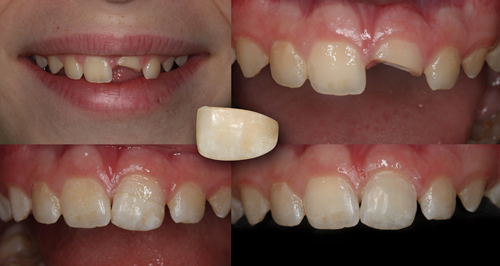

A 12-year-old male presented for a consultation for the restoration of the maxillary left central incisor (tooth No. 9), which was fractured when the patient was hit with a hockey stick while playing in gym class at school (Figs. 1 and 2). The patient had undergone endodontic treatment performed by an endodontist to stabilize the tooth one week earlier, and his parents were referred to the author via the American Academy of Cosmetic Dentistry (AACD) website.

Fig. 1 Fig. 2

Fortunately, the patient’s mother had retained the missing, fractured tooth segment (Fig. 3). Therefore, the treatment plan discussed with and accepted by the patient’s parents involved reattaching the fractured tooth segment using a universal dual-cure adhesive resin cement, G-CEM LinkForce, after which a compactable universal nano-hybrid composite, G-ænial Sculpt would be placed to directly veneer the facial and palatal surfaces of the tooth to mask the fracture line (Fig. 4).

Fig. 3 Fig. 4